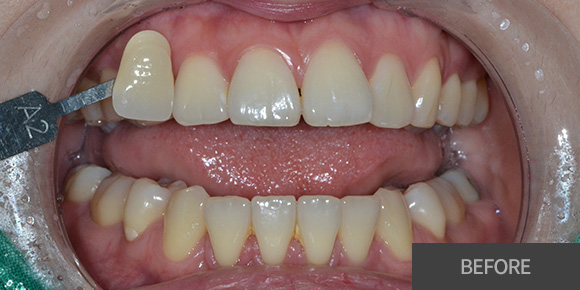

심미레진

전체미백

실활치미백